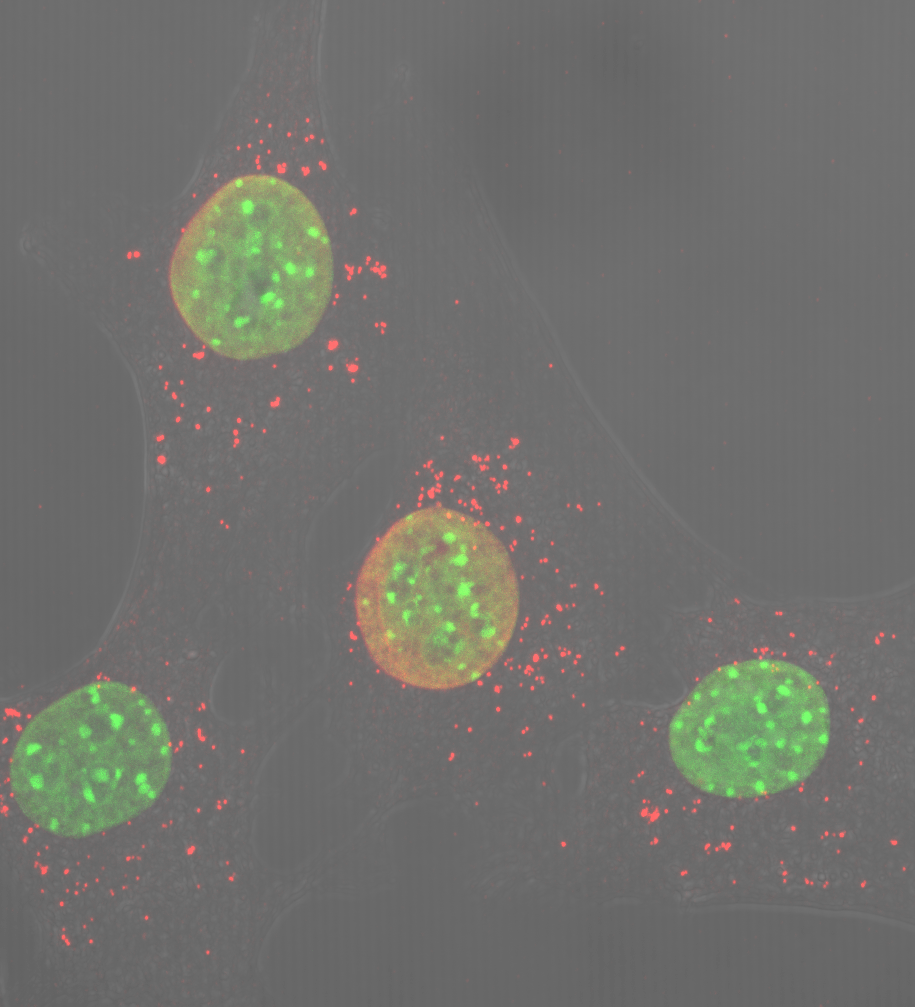

• CIBERDEM

Trabajan en una nueva estrategia para generar células productoras de insulina mediante nanofibras de péptidos autoensamblantes

06/04/2018